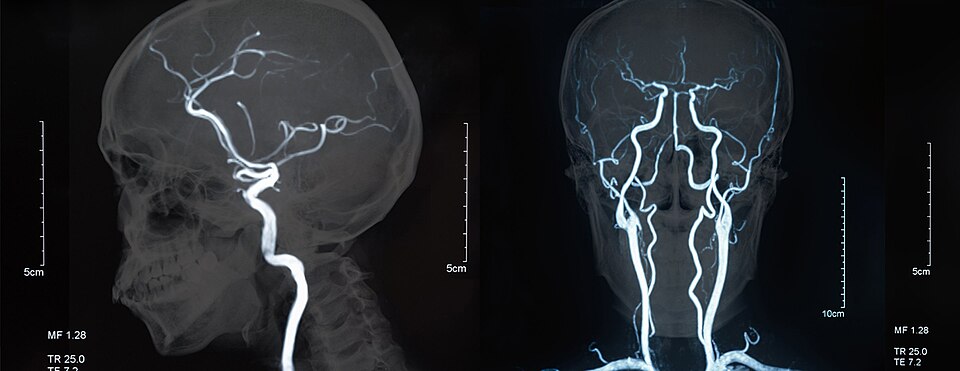

Magnetic Resonance Angiography

Magnetic Resonance Angiography (MRA) is a type of MRI scan used to visualise blood vessels and detect various vascular conditions by employing time-of-flight (TOF) and contrast-enhanced (CE) techniques. TOF-MRA is helpful for imaging arteries and veins without contrast agents, while CE-MRA uses gadolinium-based agents to enhance blood vessel visibility, providing high-resolution images quickly. MRA is used to diagnose conditions such as peripheral artery disease, renal artery stenosis, and arterial dissection, as well as to identify blood flow abnormalities, narrowing or blockages, and aneurysms.